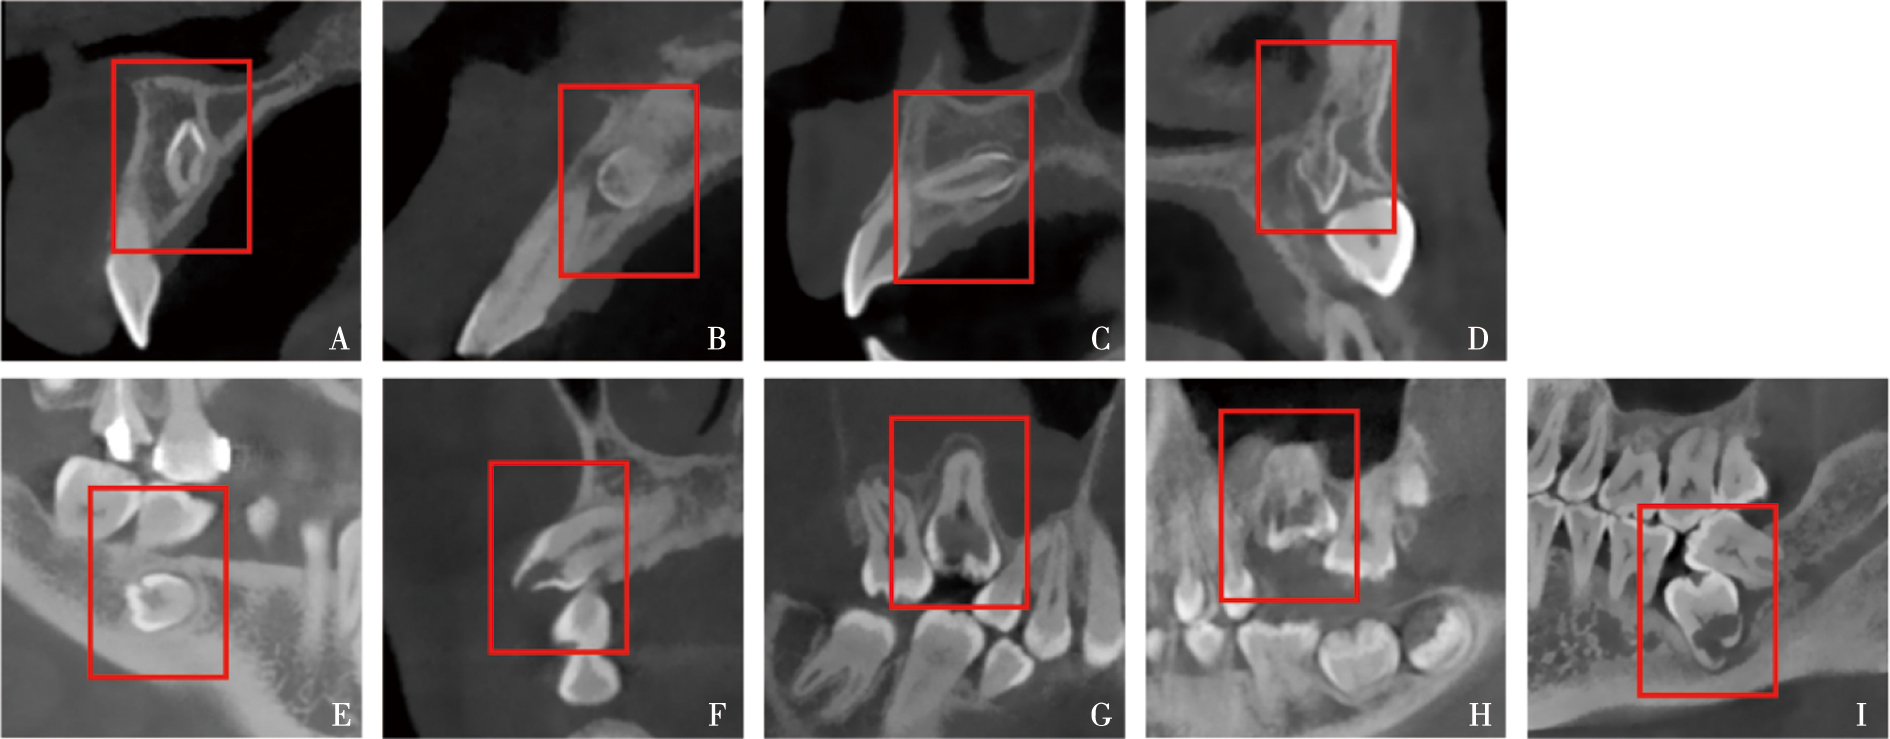

Kaasalainen T, Ekholm M, Siiskonen T, et al. Dental cone beam CT: An updated review[J]. Phys Med, 2021, 88: 193-217.

Vaz de Souza D, Schirru E, Mannocci F, et al. External cervical resorption: A comparison of the diagnostic efficacy using 2 different cone-beam computed tomographic units and periapical radiographs[J]. J Endod, 2017, 43(1): 121-125.

Rodríguez G, Abella F, Durán-Sindreu F, et al. Influence of cone-beam computed tomography in clinical decision making among specialists[J]. J Endod, 2017, 43(2): 194-199.

Rodríguez Mazón M, Garcia-Font M, Doria G, et al. Influence of cone-beam computed tomography in clinical decision-making among different specialists in external cervical resorption lesions: A before-after study[J]. J Endod, 2022, 48(9): 1121-1128.

Special Committee to Revise the Joint AAE/AAOMR Position Statement on use of CBCT in Endodontics. AAE and AAOMR joint position statement: Use of cone beam computed tomography in endodontics 2015 update[J]. Oral Surg Oral Med Oral Pathol Oral Radiol, 2015, 120(4): 508-512.

European Society of Endodontology (ESE), Patel S, Lambrechts P, et al. European society of endodontology position statement: External cervical resorption[J]. Int Endod J, 2018, 51(12): 1323-1326.